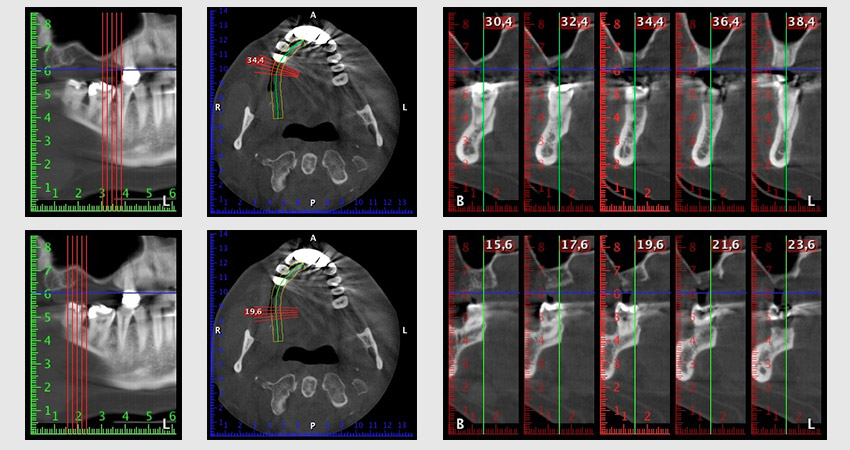

Unos seis meses después de la extracción de las piezas 16 y 14 se realizó una tomografía digital de volúmenes (DVT, Planmeca) para realizar una planificación adecuada y reducir los riesgos al mínimo. En este punto se constató que el hueso no se había regenerado en la cantidad deseada (figuras 2 a 7).

Figuras 2 a 7: Tomografía digital de volúmenes con oferta ósea horizontal reducida.